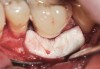

Fig 5. A surgical cover screw was placed onto the implant in order to achieve gingival augmentation in situ prior to a secondary soft-tissue procedure.

Figure 5

The following case report provides an example of this case scenario: A 28-year-old white female patient presented with her maxillary right lateral incisor significantly longer than the contralateral tooth following restoration of an existing crown that was 10 years old (Figure 3). The patient was dissatisfied with the esthetic appearance of the restoration due to the increased length, recession of the gingival tissues, and discoloration of the surrounding mucosa (Figure 4). Similar to case scenario No. 1, the first step in treatment was to decoronate the healthy implant by placing a flat surgical cover screw and employing a provisional resin-bonded-retained (RBR) prosthesis as a transitional fixed restoration (Figure 5 and Figure 6). The gingival augmentation in situ was allowed to take place for 2 to 3 weeks and was evaluated after that time (Figure 7).

Solution: Decoronate the implant by placing a surgical cover screw on it and allow the soft tissues to migrate over the coronal aspect (implant decoronation).8,20,21 A few weeks later, perform the second-stage uncovering of the implant and place a flat profiled healing or custom abutment to redirect the submergence profile or angle of the provisional crown.22 After maturation of the peri-implant mucosal soft tissues several weeks later, make the final impression and construct the definitive restoration with compensatory flat subgingival contours to allow midfacial soft-tissue stability.